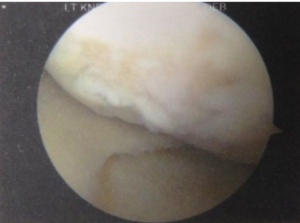

Osteoarthritis of the knee increases in frequency with age. The most common reason is because of cartilage degeneration, with decreased cellularity and reduction of the ground substance in the matrix. This results in fraying, splitting and breakdown of the cartilage. This can be seen in X-rays with narrowing joint lines. Sometimes one side of the joint can be affected more than the other, as seen in the X-ray below (fig 1). Reaction of the surrounding bone results in bone spurs (osteophytes), subchondral sclerosis and bone cyst formation, which are also usually visible on X-rays.

With damage to the cartliage (fig 2), the sensitive underlying bone is exposed. The bone contains senstive nerve endings which are no longer protected by the artilage, and over-stress with lead to pain.